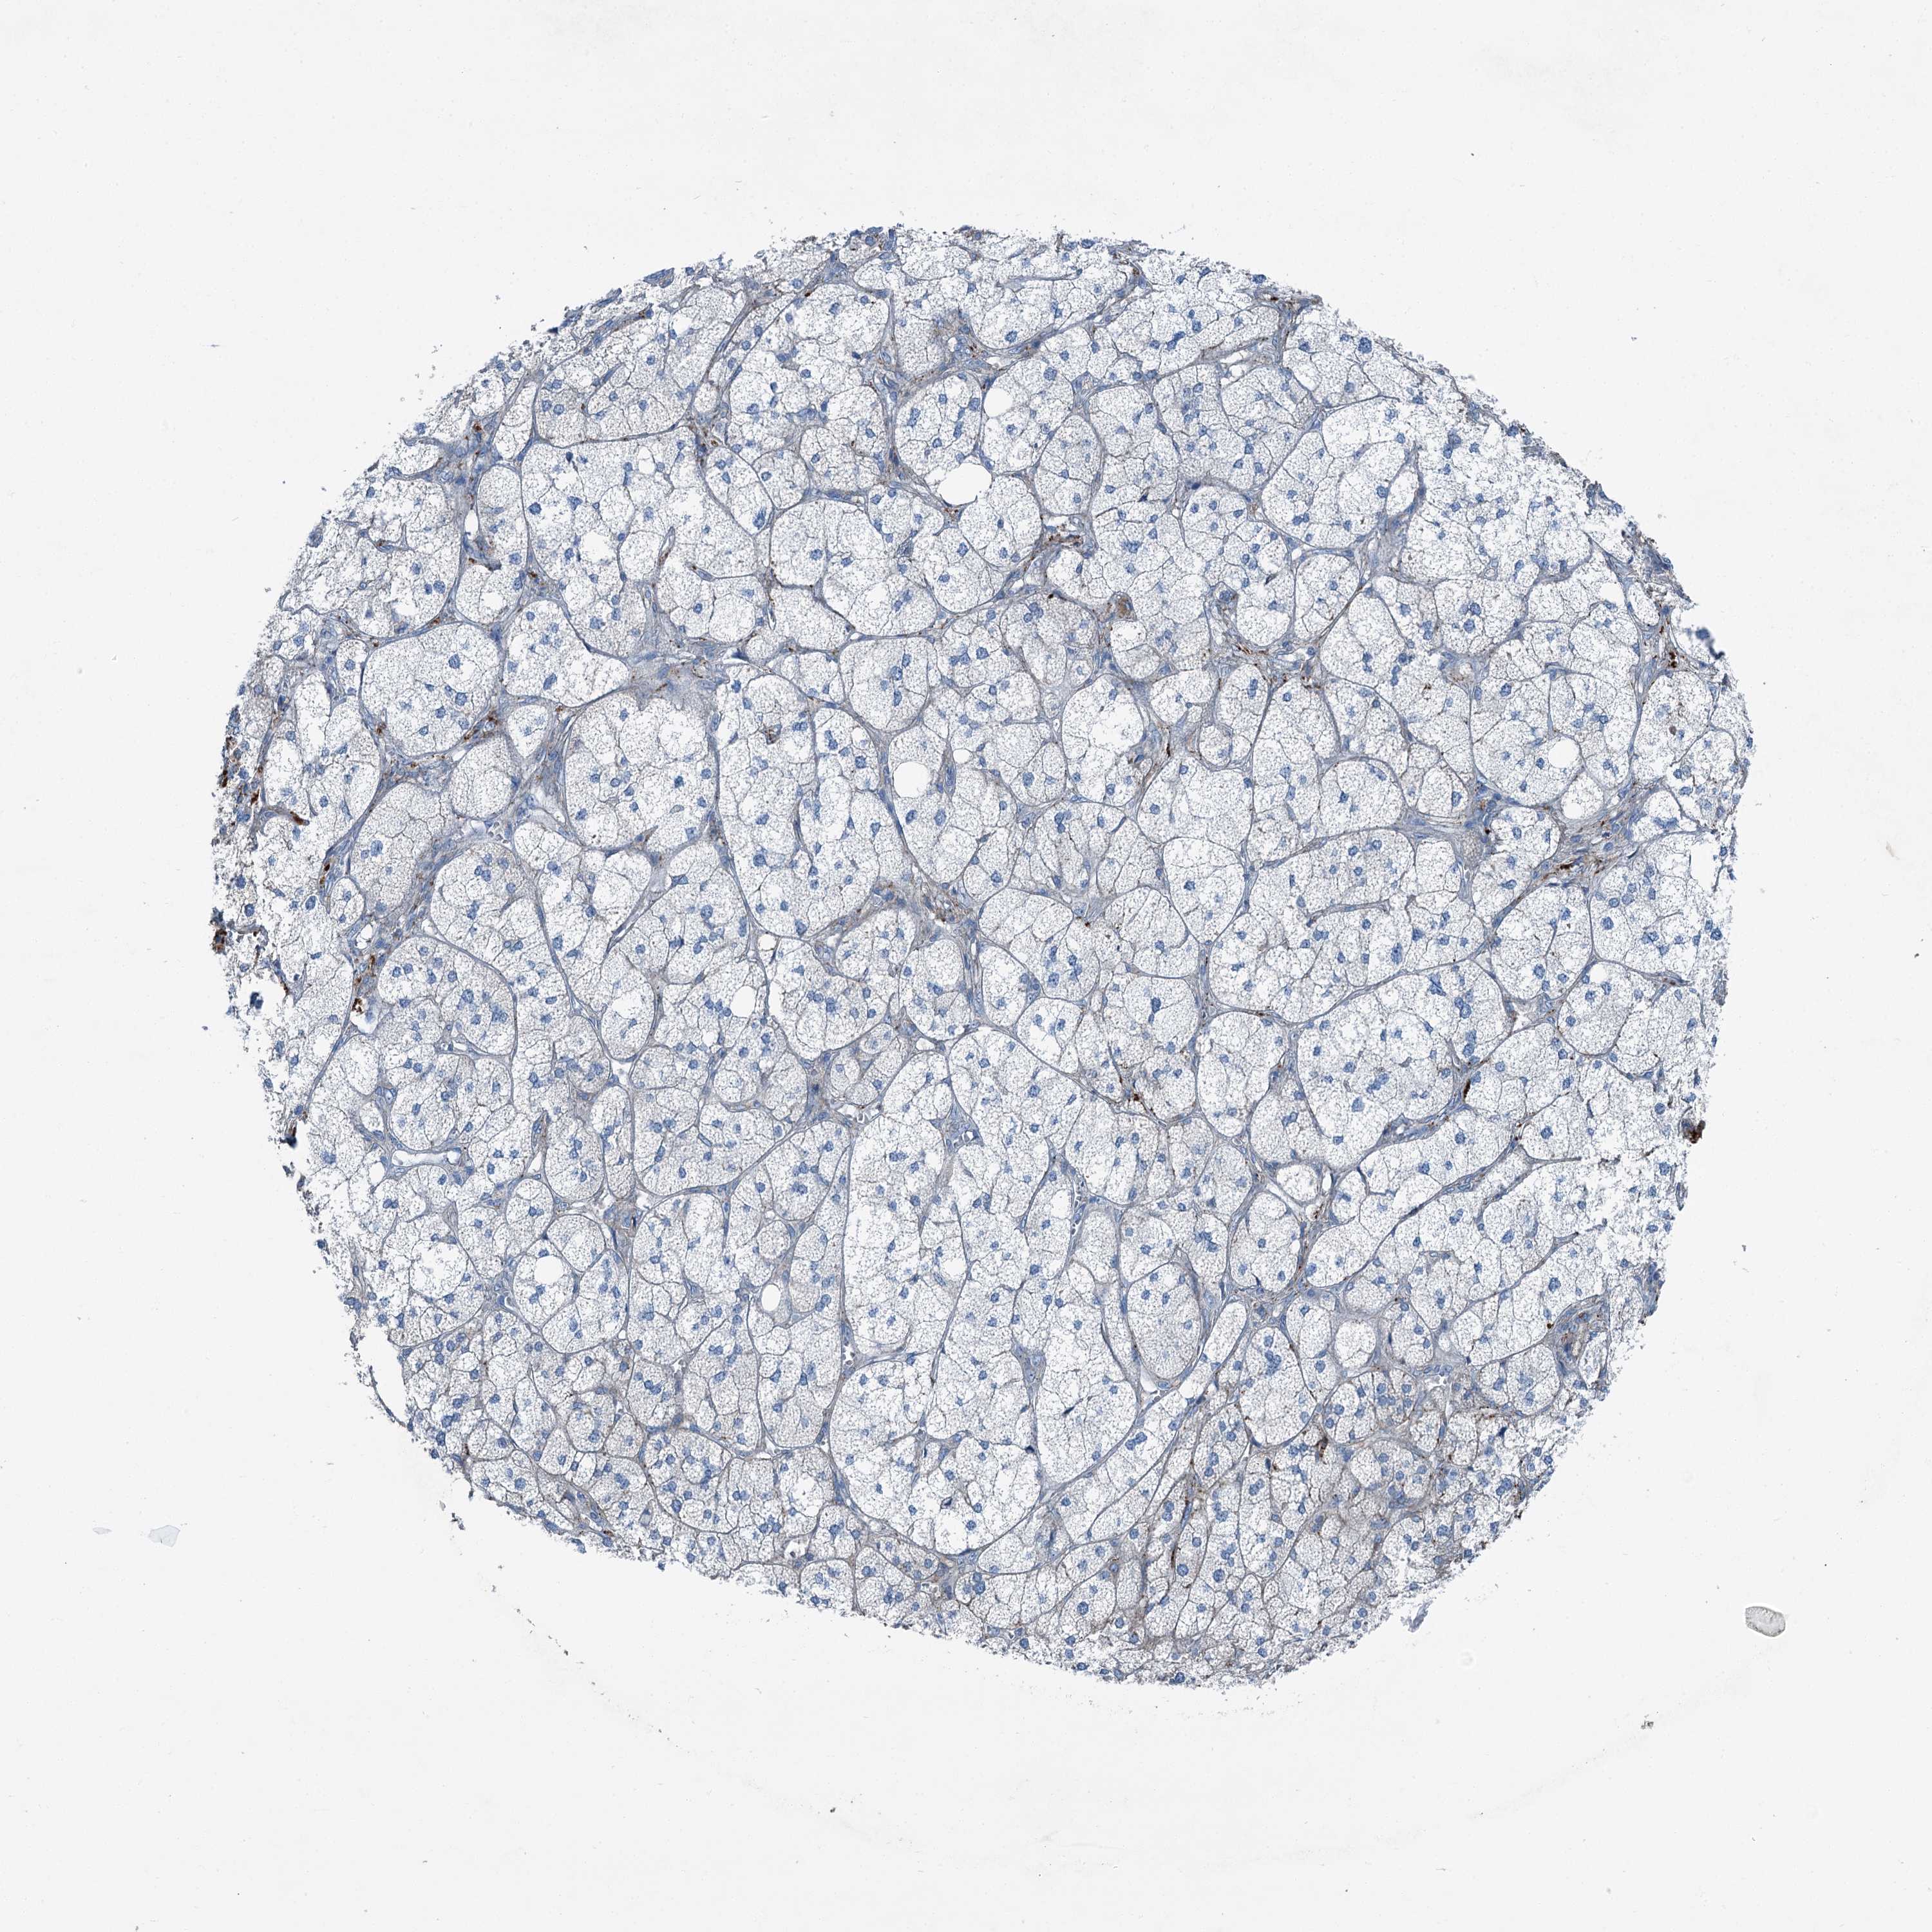

ADRENAL GLAND - Antibody stainingi

Antibody staining in the annotated cell types in the current human tissue is reported as not detected, low, medium, or high, based on conventional immunohistochemistry profiling in selected tissues. This score is based on the combination of the staining intensity and fraction of stained cells.

Each image is clickable and will lead to virtual microscopy that enables deeper exploration of all samples and also displays staining intensity scores, fraction scores and subcellular localization as well as patient and tissue information for each sample.

Antibody HPA037422Antibody HPA037423Antibody CAB032501

Glandular cells Not detectedNot detectedMedium